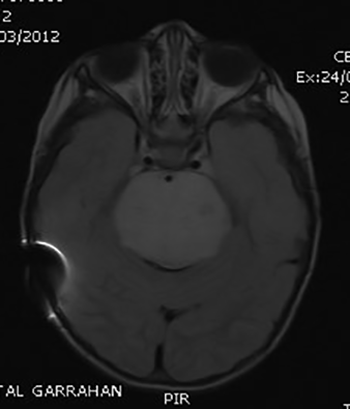

En caso de lesiones no difusas en las cuales, por diversos motivos, no es posible la terapéutica quirúrgica, la posibilidad de obtener material permite administrar tratamiento médico en especial ante la presencia de marcadores moleculares con terapias específicas como es el caso de gliomas con mutación BRAF V600E1,3,21 (Figura 3).

Figura 3: IRMN T1. Tumor en mescencéfalo heterogéneo, dada la alta morbilidad quirúrgica fue realizada una biopsia estereotáctica dando como resultado astrocitoma de bajo grado.